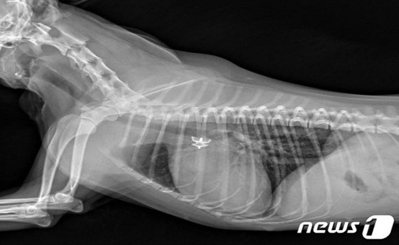

"침대 조심하세요"…강아지 낙상 후 골절된 앞다리 치료법은 [VIP벳]VIP동물의료센터 청담점 치료 사례강아지 상완골 관절 융기 골절 재건술은말티푸 종의 강아지 철이(가명, 1년 10개월)는 침대에서 떨어진 이후 오른쪽 앞다리를 딛지 못하고 아파하는 증상을 보였다. 동물병원에서 방사선 검사상 오른쪽 주관절(사람으로 치면 팔꿈치, 해부학명 shoulder elbow)의 골절과 탈구가 확인됐다. 철이는 곧바로 수술받았고 현재는 회복해 건강하게 지내고 있다.VIP동물의료센터에 따르면 강아지 주관절 골절은 침대나 소파에서 떨어지거나 큰 충격을 받았을 때 주로 발생한다. 골절 이후 강아지는 통증으로 인해 걷지 못하게 되고 고통도 호소한다.[낙상으로 인해 오른쪽 앞다리 골절상을 입은 강아지의 엑스레이 사진]강아지 주관절 골절 치료의 경우 골절편을 정상 해부학적 구조로 맞춘 후 다양한 재료를 사용해 고정할 수 있다. 나사를 사용하거나 핀을 사용할 수 있는데 환자(환견) 뼈의 크기 및 상태, 주변 근육이나 연부 조직의 상태, 개체별 성향, 기저질환 및 여러 요소를 고려해 적절한 재료를 선택해야 한다.치료를 위한 이식물을 삽입하는데 있어 고정과 안착이 잘 돼야 한다. 주변 조직에도 자극이 되지 않아야 하므로 수술 전 철저한 수술 계획을 세우는 것이 중요하다.철이도 이 같은 사항을 고려해 계획하에 수술을 진행했다.철이의 환부 주변 근육을 충분히 이완시키고 뼈를 원위치에 맞춰 수제로 고정한 후 스크류와 핀을 삽입했다. 골절로 인해 생길 수 있는 염증을 관리해주기 위해 멸균생리식염수로 수술 부위를 충분히 세척하는 과정도 거쳤다.[강아지의 앞다리 수술 후 촬영한 엑스레이 사진(VIP동물의료센터 제공)] 수술 후 검사를 통해 골절된 뼈가 잘 교정된 것을 확인했다. 이식물도 목표한 대로 잘 장착됐다. 이후 대칭적 부중 치료를 위한 짐볼 재활치료와 수술 부위 회복을 위한 냉각치료, 레이저치료를 진행했다. 철이는 2주차부터 정상 보행이 가능해졌다.[김종인 VIP동물의료센터 청담점 원장 ⓒ 뉴스1]김종인 원장은 "강아지 주관절이 골절된 경우 신속하고 정확하게 계획해 수술을 하는 것이 중요하다"며 "철이의 경우 골절 후 시간이 경과된 시기에 수술이 진행돼 주변 조직이 구축되다보니 골절부의 환납이 어려웠다. 하지만 적절히 수술해 주변조직을 최대한 보존하며 성공적으로 수술을 마칠 수 있었다"고 밝혔다.이어 "사람과 마찬가지로 강아지 다리 골절이 발생한 경우 최대한 빠르게 병원에 내원해 치료를 받을 것을 권한다"고 조언했다....기사 자세히 보기